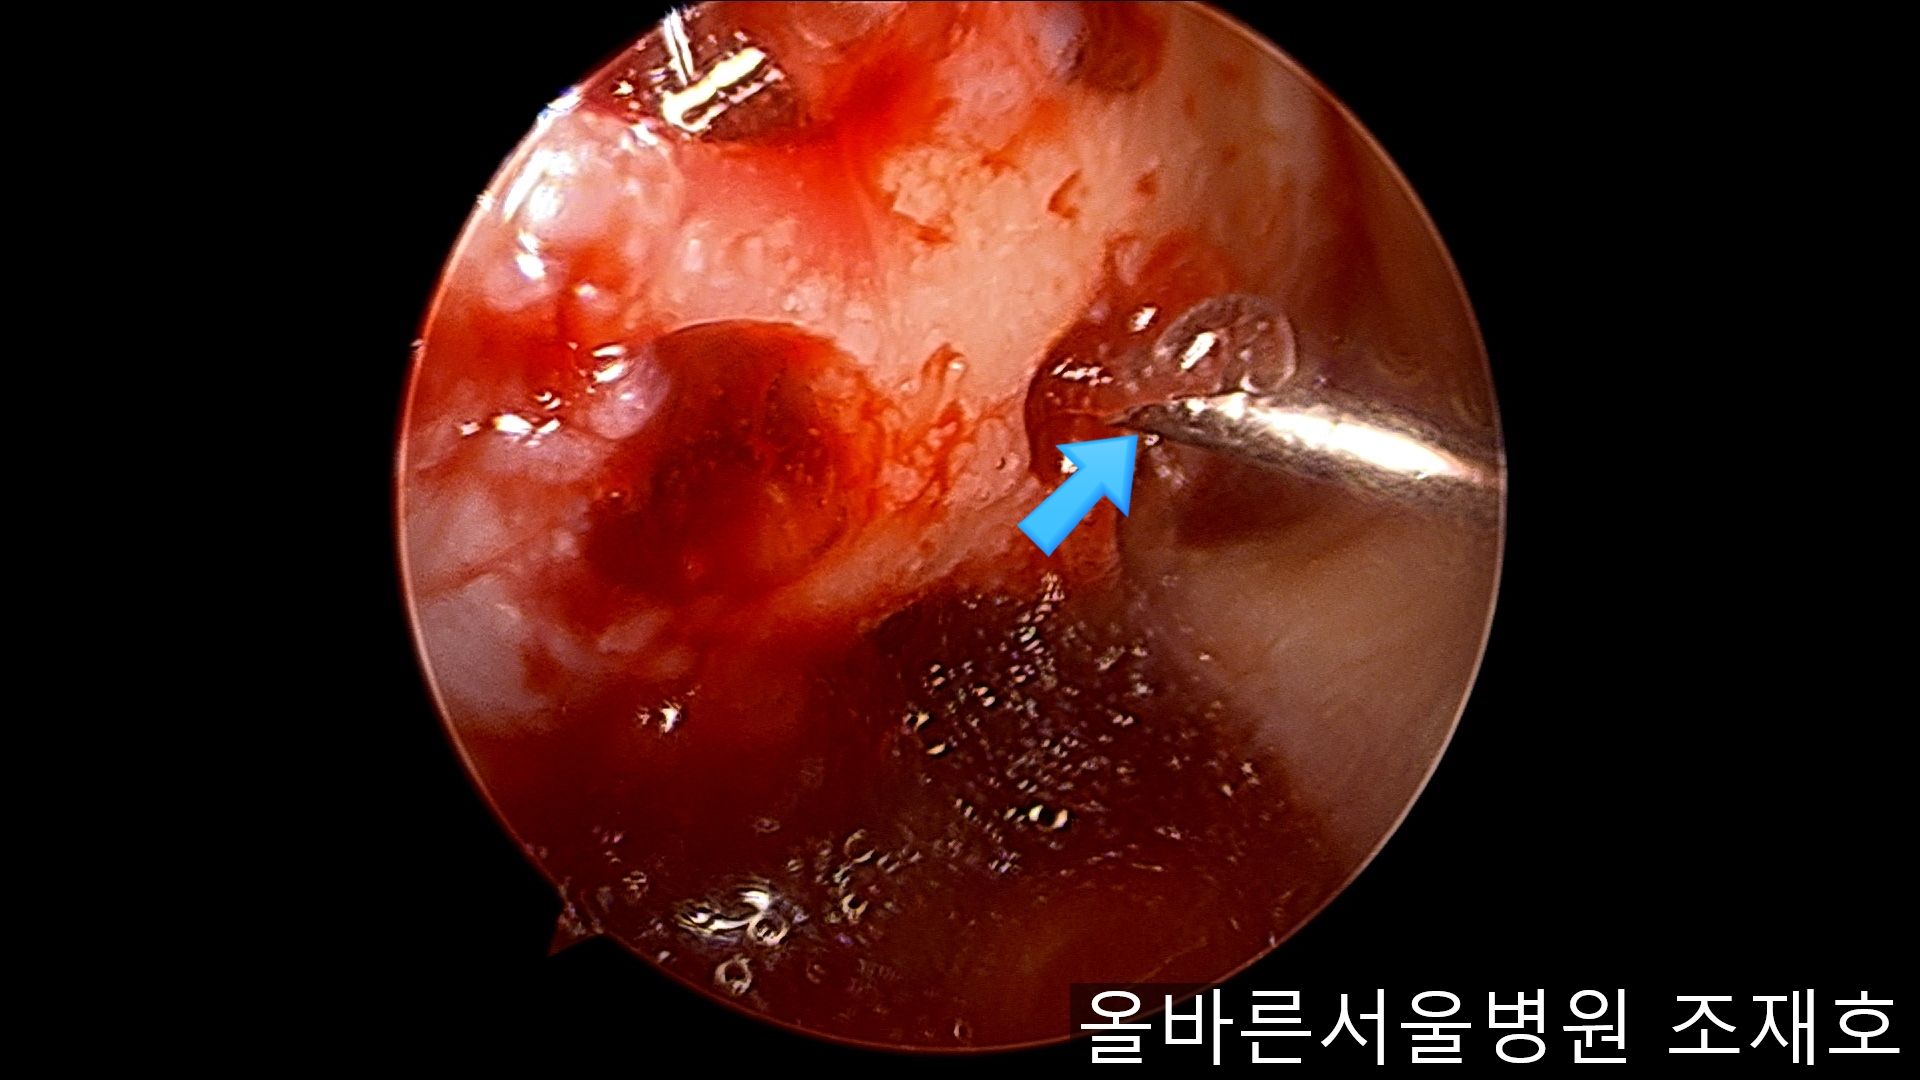

通过关节镜图像可看到:由于内侧股骨髁软骨损伤骨头已经显露出来。

胫骨上端的软骨损伤严重,也露出了骨头。

正是缺失软骨的部位碰到一起,引发剧烈疼痛,腿部逐渐变形。

为了软骨再生,在胫骨上端进行微骨折术。

胫骨上端是通过微骨折术,可再生软骨的地方。

尽量将孔打地细密,确认此处骨髓腔内的血流出。

在股骨部位用CARTISTEM注射用4mm激光钻细密打孔,并确保软骨板不倒塌。不用切开通过关节镜即可完成手术。

如图,尽量细密打孔。